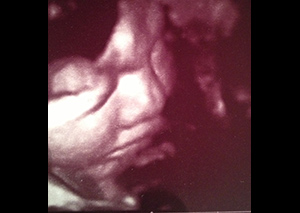

W nowoczesnych wysokiej klasy aparatach ultrasonograficznych istnieje możliwość przetwarzania danych z badania dwuwymiarowego co umożliwia pokazywanie obrazów trójwymiarowych badanych struktur płodu w czasie rzeczywistym.

Ultrasonografia trójwymiarowa 3D pozwala na uzyskanie statycznych obrazów przestrzennych, które otrzymywane są w procesie obróbki komputerowej danych z badania dwuwymiarowego. Ultrasonografia 4D pozwala na uwidocznienie dynamicznego przestrzennego obrazu.

Ta nowa prezentacja (prezentacja 4D) pochodzi od dodania czwartego wymiaru jakim jest czas. Badanie płodu metodą 4D pozwala nie tylko na obrazowanie przestrzenne płodu ale również pozwala na obserwację ruchów twarzy, obserwację otwierania i zamykania oczu, ruchów języka, ssania palców. Przy korzystnym ułożeniu płodu, w odpowiednim wieku ciążowym ( najlepiej pomiędzy 15. a 35. tygodniem ciąży) możliwa jest diagnostyka szeregu wad rozwojowych płodu. Badanie 4D pozwala też na precyzyjne obrazowanie rozwoju płodu i umożliwia podejrzenie wyglądu dziecka, którego wygląd jest niemal identyczny z jego rzeczywistym wyglądem.

Zastosowanie techniki 3D i 4D ma szczególne zastosowanie w położnictwie. Umożliwiają precyzyjną ocenę narządów wewnętrznych płodu, np. serca, mózgowia, kręgosłupa, twarzy oraz w sposób istotny pozwalają na zwiększenie wykrywalności wad budowy płodu .